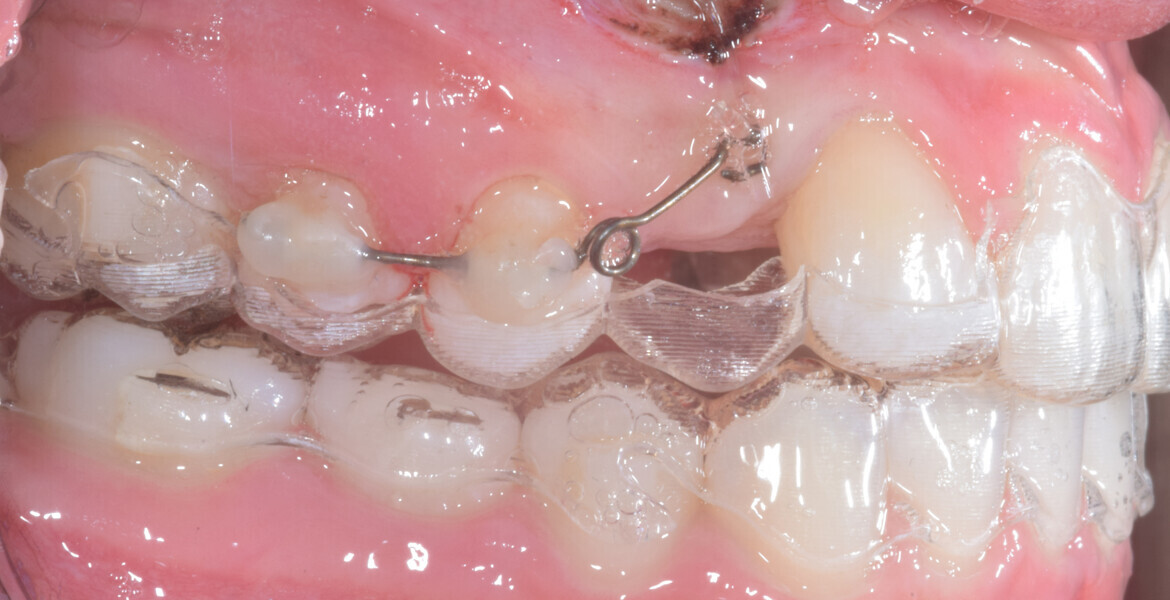

At the end of the first stage of aligner treatment (Figs. 20–24), the auxiliary phase began with the bonding of two MTAs on the maxillary right premolars. A 0.016-in Australian archwire, shaped into a cantilever configuration, was then inserted into the MTAs, and a cutout was created on the final aligner. To prevent rotation, the archwire was cinched distal to tooth #15 and the cinch covered with composite.

At the same time, the impacted canine was exposed by laser, a button was bonded on to it and the cantilever was connected to the button using an elastomeric thread. The final aligner was used for space maintenance while the cantilever was reactivated until the canine had erupted (Figs. 25–27). After complete eruption, further MTAs were bonded on the canine and on the lateral incisor, and a 0.014 in. NiTi archwire was used to finalise the eruption (Figs. 28–30). Only at the end of the forced eruption phase did the further aligner stage take place, aimed at achieving an ideal Class I relationship on the right by maxillary right mesialisation using Class III elastics and 27 maxillary aligners and 13 mandibular aligners (Figs. 31–33).